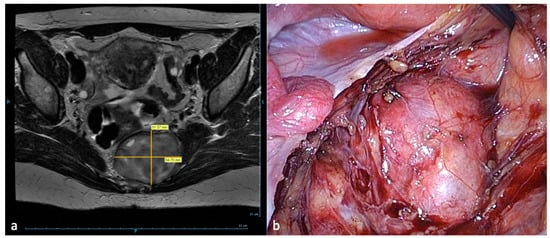

- Possover, M. Laparoscopic therapy for endometriosis and vascular entrapment of sacral plexus. Fertil. Steril. 2011, 95, 756–758. [Google Scholar] [CrossRef]

- Possover, M.; Forman, A. Pelvic Neuralgias by Neuro-Vascular Entrapment: Anatomical Findings in a Series of 97 Consecutive Patients Treated by Laparoscopic Nerve Decompression. Pain Physician 2015, 18, E1139–E1143. [Google Scholar]

- Possover, M. Five-Year Follow-Up after Laparoscopic Large Nerve Resection for Deep Infiltrating Sciatic Nerve Endometriosis. J. Minim. Invasive Gynecol. 2017, 24, 822–826. [Google Scholar] [CrossRef] [PubMed]